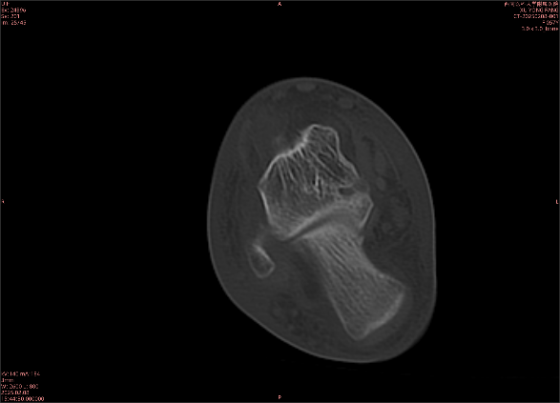

舉例圖像

圖1

專業(yè)解釋看不懂沒關(guān)系,大家看圖1和圖2就可以了,這是同一個(gè)患者跟骨的磁共振和CT圖像,圖1的紅色箭頭指示的黑線就是磁共振圖像顯示的骨折線,一目了然。而對(duì)比圖2的CT圖像上并未顯示異常。